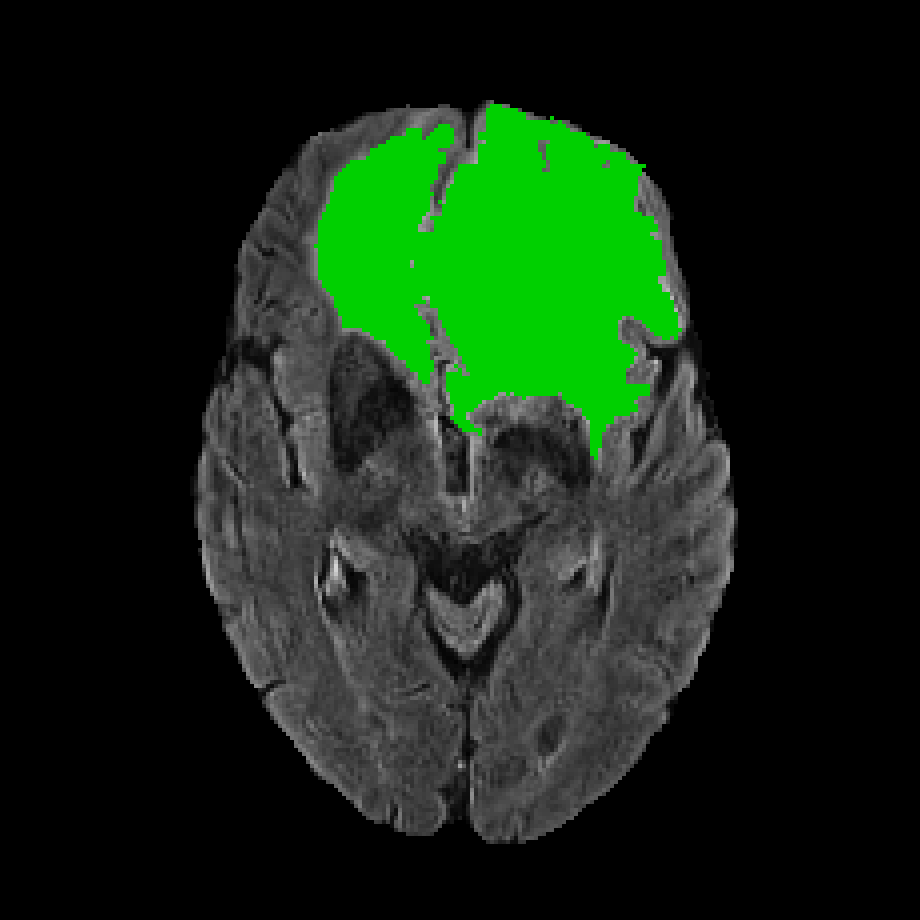

In subsection 4.3, the demonstration experiment verifies that our proposed redundancy filtering is efficient. In CIML, the extracted information representations are high-dimensional features, and to visualize the complementary information, we use the Grad-CAM algorithm to get class-discriminative localization maps (we will refer to it as a heatmap when there is no possibility of confusion) that highlight the voxels focused on by our proposed CIML algorithm.

In deep convolutional networks, the deeper layers typically extract semantic information but lose positional correspondence. Conversely, the shallower layers are able to extract detailed pattern information while preserving positional correspondence. Therefore, in order to maintain a clear understanding of positional information, we choose to visualize the information representations from the shallowest layers of the network, which have the same resolutions as the images with channels. In the BraTS2020 dataset, we default decompose segmentation into four segmentors. Additionally, there are six modality target region pairs. For -th pair, let be the information representations (with channels), and be the logit for a chosen pixel class . Grad-CAM averages the partial gradients of with respect to voxels of each information representation. The heatmap for class in pair

where is the neuron importance weights of the channel of information representations for pair .

In Figure 12, we visualize information representations extracted from the last messages by applying heatmaps as masks added to the original images. The last message refers to the shallow embedding in the neural network, which is the message with the highest resolution. We normalize the heatmaps across all rows so that the amount of information in each auxiliary modality can be easily compared. Yellow represents the largest value, dark blue represents the smallest value, and light blue represents the middle value. As shown in the first row, FLAIR is the primary modality, and the T2 image contains the most complementary information compared to the other two modalities. In the second row, T2 is the primary modality, and the FLAIR image contains the most complementary information. Additionally, the left-down region of the FLAIR image contains more information, which is consistent with medical domain knowledge. This region, depicted in hyperintensity (lighter in source images), indicates the presence of edema, typically locates at the periphery of the WT. The third and fourth rows illustrate TC is the target region and the hyperintensity regions in T1CE, which means ET regions, contain the most information. In the final two rows concerning T1CE as the primary modality, it is observed that auxiliary modalities contribute less information overall. However, the T2 image still provides some valuable complementary insights, particularly in the hyperintense areas, which appear as low-intensity zones in the T1CE image indicating the necrotic and non-enhancing tumor core. These results demonstrate that the results predicted by our proposed CIML methods are consistent with the physician’s domain knowledge and permit further verification that the algorithm can extract complementary information from high-dimensional data.